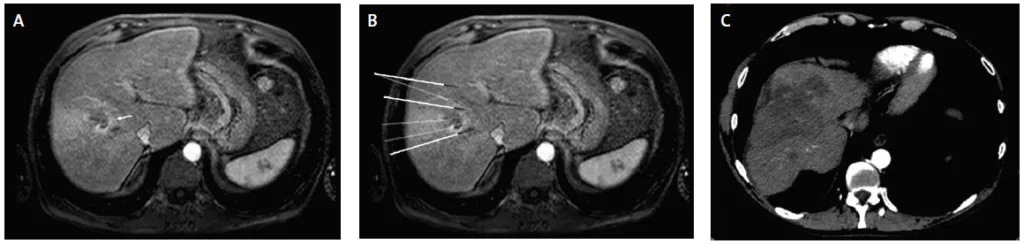

Figure 4. Ablation par electroporation irréversible d’un CHC infiltrant du foie droit avec envahissement portale Vp3

A. IRM axiale au temps artériel de l’injection intraveineuse de gadolinium montrant une tumeur mal limitée du foie droit responsable d’un envahissement de la branche portale droite (Vp3) ainsi que des branches sectorielles antérieur et postérieur (flèche).

B. IRM axiale au temps artériel de l’injection intraveineuse de gadolinium réalisée un mois après une ablation par électroporation avec six aiguilles (implantations par abord latéral selon l’axe de branche portale droite. Cf : figure 2) montrant une excellente réponse avec la disparition de la prise de contraste du thrombus tumorale.

C. Même coupe IRM qu’en B au temps portale de l’injection montrant la perméabilité conservée de la branche portale gauche et l’absence de dommage de la convergence biliaire principale bien que l’ablation ait été réalisée au contact de ces éléments nobles.